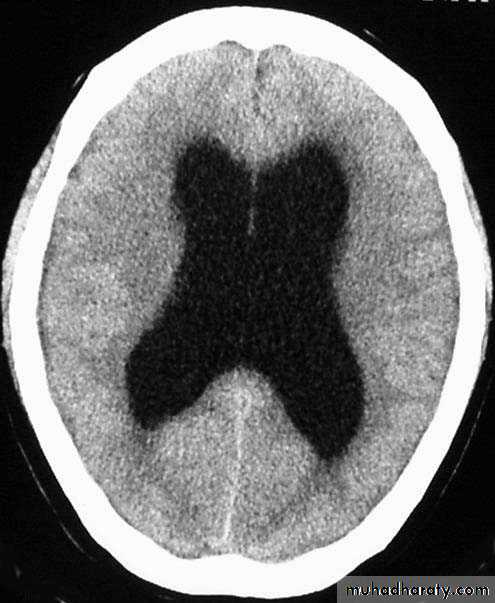

Hydrocephalus

36

Hydrocephalous

• accumulation of cerebrospinal fluid (CSF) in the ventricles, or cavities, of the brain .

• two types :

• communicating hydrocephalous :

• fluid flows from the ventricular system into the subarachnoid space.

• In communicating type blockage is in the subarchnoid space by blockage of arachnoidal villi themselves .

• Hydrocephalous

• Non communicating :• Fluid cant pass to the subarachnoid space

• In this type is blockage of the aqueduct of sylvius .

• Obstruction of villi blockage ↑ CSF pressure hydrocephalous may lead to edema .